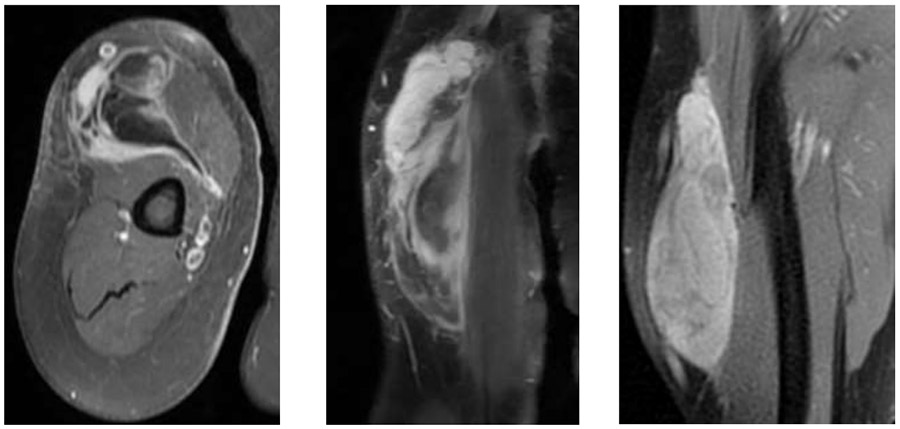

Ameliyat Öncesi: MR’da kol ön kısımda sınırları düzensiz heterojen yumuşak doku kitlesi görülmekte